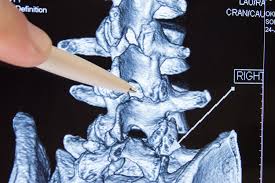

Kann das denn überhaupt möglich sein. Da ich keine weitere Operation möchte da sowas sehr problematisch sein kann wenn nochmal eine Operation zur Reduktion von. Im Prinzip geht niemand gerne an eine voroperierte Wirbelsäule.

Es kann vorkommen dass nach einer Wirbelsäulen OP Narbengewebe die Nerven bedrängt und das zu erneuten Schmerzen führt. Diese treten typischerweise einige Zeit nach der Operation auf Narben brauchen Zeit sich zu bilden.